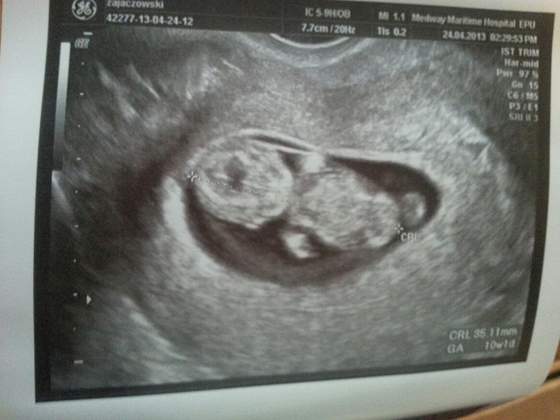

wstawie Wam zdjęcie naszego Bejbika z 10 tyg, taki mały okruszek a od samego początku rządzi ;-)